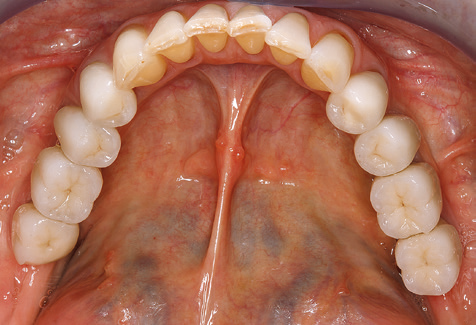

Un paziente di 52 anni si è presentato nella nostra clinica per la prima volta nel 2004 a seguito della perdita dei denti nel terzo quadrante, esprimendo il desiderio di un nuovo restauro protesico. La diagnostica parodontale e radiologica ha rivelato la necessità di un ampio trattamento parodontologico. Inoltre, ai denti 48, 28 e 27 è stata attribuita una prognosi molto scarsa e sono stati successivamente estratti (Fig. 1). A seguito del trattamento periodontologico sistematico completato con successo, è stato inserito una protesi dentale fissa con l'inserimento di cinque impianti nelle regioni dentali 35, 36, 37, 46 e 47. Il trattamento protesico dei denti naturali è stato effettuato con corone rivestite in ceramica di biossido di zirconio; gli impianti two-piece composti da abutment singoli in biossido di zirconio e corone similmente rivestite in ceramica di biossido di zirconio (base Cercon colorata, Dentsply Sirona Lab). L'inserimento definitivo del restauro protesico è avvenuto nel 2005.

A causa della presenza di problematica parodontale, SPT è stata eseguita ogni tre mesi nei primi anni successivi all'inserimento. Il paziente ha dimostrato un alto grado di motivazione e una buona costanza. Le profondità di tasca registrate ogni anno hanno rivelato una situazione parodontale stabile con un indice BOP inferiore al cinque per cento. Sulla base della situazione parodontale stabile e della buona collaborazione da parte del paziente, l'intervallo di richiamo è stato esteso ogni sei mesi a partire dal sesto anno dalla fase della funzione protesica. A seguito della modifica dell'intervallo di richiamo, la rispettiva documentazione annuale dello stato parodontale ha continuato a rivelare una situazione parodontale stabile senza aumento della profondità della tasca e un indice BOP inferiore al cinque per cento (Fig. 2a eb).

Il controllo decennale non ha rivelato alcuna indicazione dell'avanzamento della perdita di attaccamento clinico o della perdita di sostanza ossea perimplantare (Fig. 3).